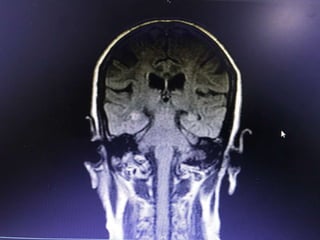

HOPI • Patient wasapparently normal till 5pm 3/2/18, started behaving abnormally like half dressed, with carrying comb and want to go temple, with irrelevant talks. • Relatives observed paucity of left Upper and lower limb, thinking of stroke - took her to near by hospital • Asked for imaging - after imaging she developed 2 episodes of left sided jerky movements of both UL & LL with twitching over the face - lasted for 1-2 min, treated with sedative , Inj. insulin for high CBG - 495 mg/dl and referred here for further management.

Provisional Diagnosis • ?Acuteischemic stroke - left hemiparesis with focal seizures • ? Hyperglycemic encephalopathy • ? Viral encephalitis

Investigations • HB- 14.1gm%- 12.2 • WBC- 15990cells/cumm - 10770, -P 83%, L-9%,M-7% • Platelets - 3.3lakhs - 2.8 • ESR- 63mm/hr • RBS - 267 mg/dl • CUE - N • RFT - N • LFT - N • S.Na - 137, k+ - 3.9, Mg- 2.1, Ca- 9.1, Ph- 3.5, Ammonia- 0.29

• ECG -N • 2DEcho- N • U/S - Abd- Gr I Fatty liver changes